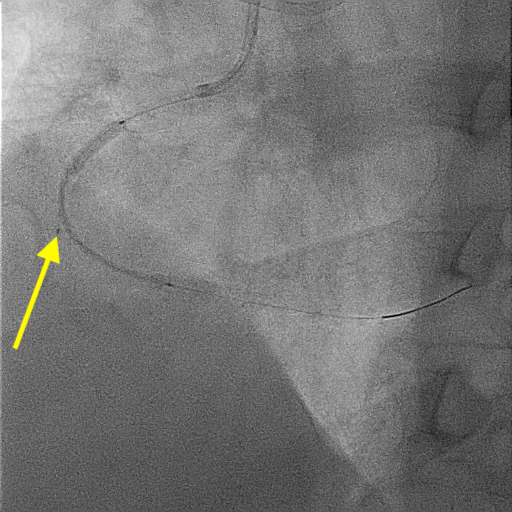

A 51-year-old man presented with stable angina and previously failed right coronary artery (RCA) CTO PCI. During RCA CTO PCI (Figure 1), the wire was inserted into the extraplaque space (Figure 2, Video 1). Intravascular ultrasound (IVUS) showed a hematoma (Figure 3A, Video 2). Live 3-dimensional tip detection IVUS wiring was successful (Figure 4, Video 3). A FineCross microcatheter (Terumo) was placed over the first wire into the extraplaque space and blood was withdrawn by connecting a negative indeflator to the microcatheter. Stents were deployed (Figure 5) and postdilated. Post-IVUS showed almost complete resolution of the hematoma (Figure 3B, C; Video 4) with good results (Figure 6, Video 5).